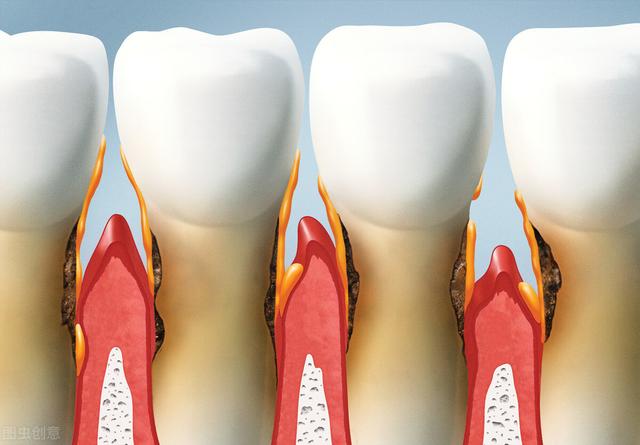

Le cancer des gencives n'est pas évident au début, comme une petite bosse, qui est généralement facile à négliger, puis il grandit un peu, s'ulcère et saigne facilement. À ce moment-là, certaines personnes pensent qu'il s'agit d'un mauvais brossage des dents, qu'il s'agisse d'une gingivite ou d'une parodontite, et elles se brossent donc les dents sérieusement ou achètent un dentifrice anti-inflammatoire et hémostatique.

Ces derniers, même s'ils contiennent des anti-inflammatoires, ne peuvent rien faire, le gonflement de l'ulcère continue à s'étendre et progresse même jusqu'à l'os alvéolaire, l'os alvéolaire est absorbé, les dents semblent se déchausser et tomber, et continuent à se développer, ce qui peut également entraîner un élargissement du visage, des difficultés à mâcher, à ouvrir la bouche, etc.

2、Type ulcératif ou exogène : le cancer gingival peut se manifester cliniquement comme un type ulcératif ou exogène, le type ulcératif étant le plus fréquent. Le point de départ se situe principalement au niveau des papilles interdentaires et de la zone de la marge gingivale. Les ulcères sont superficiels et rougeâtres, et plus tard, une hyperplasie peut apparaître. Le mucopérioste et le processus alvéolaire étant très étroitement liés, il est plus facile d'envahir le périoste et l'os du processus alvéolaire à un stade précoce, ce qui entraîne le déchaussement de la dent, qui peut se détacher.

3. propagation et destruction : quel que soit le point de départ du cancer gingival, du côté buccal (lèvre) ou palatin (langue), il peut s'étendre au côté opposé par la zone interdentaire ; du côté extérieur, chaque côté envahit la lèvre et le sillon de la joue, tandis que du côté intérieur, chaque côté envahit le fond de la bouche et le palais ; vers le haut, il peut détruire le fond du sinus maxillaire, pénétrer à travers l'os et pénétrer dans le sinus primitif supérieur, ce qui deviendra le cancer secondaire du sinus maxillaire ; vers le bas, il peut affecter l'os de la mâchoire et, à un stade avancé, il peut même provoquer une fracture pathologique. Après l'invasion de l'os par le cancer gingival, les radiographies peuvent montrer une résorption irrégulière comme un vermifuge, ce qui est la caractéristique destructrice d'une tumeur maligne.

Au stade précoce du cancer des gencives, la propagation et l'invasion des tissus cancéreux provoquent le déchaussement des dents et des douleurs. Lorsque le cancer gingival progresse graduellement, le tissu cancéreux envahit le sillon labiobuccal, le plancher de la bouche, la muqueuse palatine, le sinus maxillaire et la mandibule, et lorsque le nerf alvéolaire inférieur est touché, il peut provoquer un engourdissement de la lèvre inférieure du côté affecté. Lorsque la tumeur envahit la région des molaires postérieures, le pharynx et le groupe des muscles masticateurs, elle peut limiter l'ouverture de la bouche, et une fracture pathologique peut être causée par une destruction sévère de l'os de la mâchoire. Au stade avancé du cancer gingival, il provoque souvent des symptômes et des manifestations systémiques, tels que l'hypercalcémie et la leucocytose, qui se manifestent par une faiblesse, des nausées et des vomissements, des douleurs abdominales et d'autres manifestations.